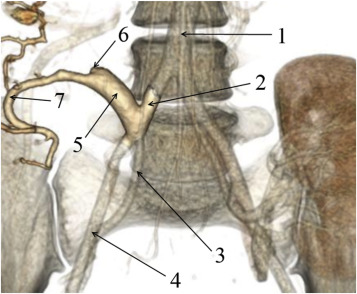

One patient (Patient 14) was diagnosed with partial nonocclusive thrombosis of both portal vein (up to 75% of the lumen) and splenic vein of the graft, and one patient (Patient 28) developed distal thrombosis of the transplant splenic vein. Ultrasound screening identified thrombosis of the upper mesenteric artery of the transplant in five patients (Patients 21, 34, 36, 37, and 39). This was subsequently confirmed by computed tomography (Figure 1).

Abdominal computed tomography (Patient 34): (1) aorta; (2) common iliac artery; ...

Abdominal computed tomography (Patient 34): (1) aorta; (2) common iliac artery; (3) internal iliac artery; (4) external iliac artery; (5) pancreas transplant Y-graft; (6) filling defect in the region of the superior mesenteric artery of the pancreas transplant; (7) splenic artery.